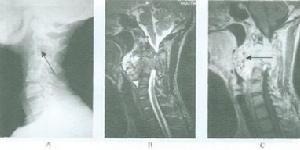

普通X線檢查中,頸椎側位片和矢狀面的斷層對Ⅰ型骨折的診斷非常有用。側位片可顯示骨折線通過樞椎椎體背側,椎體的前方大部分和寰椎一道向前移位,並伴屈曲或伸展的成角畸形,而其椎體後、下部位仍在原處,位於C3椎體上方的正常位置,斷層以片可清楚顯示骨折線及骨折塊移位的情況。開口位片和冠狀面的斷層片對Ⅱ型骨折的診斷非常有價值,可顯示樞椎側塊塌陷、寰椎側塊進入樞椎上關節面。

CT尤其是CT三維重建對了解骨折的全面信息非常重要。

MRI對軟組織的良好解析度使其在脊髓損傷中使用廣泛;同樣,在樞椎椎體骨折患者中,MRI可清楚顯示脊髓損傷和受壓的情況。